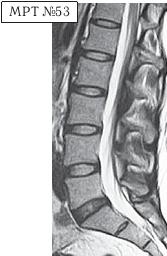

На МРТ № 53 — поясничный отдел позвоночника.

На данном «контрольном» снимке, после устранения методом вертеброревитологии секвестрированной грыжи межпозвонкового диска в сегменте LV-SI, наблюдаются остаточные явления дегенеративного процесса. Но в целом состояние поясничного отдела позвоночника, отображённое на этом снимке, довольно хорошее, поэтому будем использовать его для сравнения как вариант нормы.